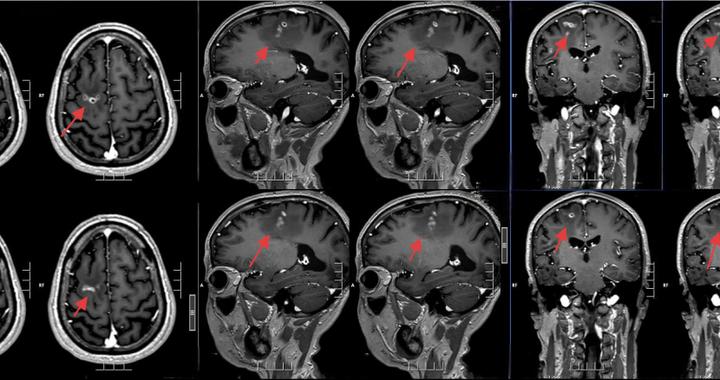

脑袋里“挖”出8厘米活虫!这个“土方子”害人不浅,很多人还在用! 最终医生在影像中发现关键线索:病灶会“移动”,还留下了“隧道”痕迹——这是虫子在脑里爬行的罪证。开颅手术后医生成功捕获一条8厘米长的活虫:裂头蚴被称为会“打隧道”的寄生虫图源:百度百科图中长得很像金针菇的虫子就是裂头蚴是曼氏迭宫绦虫的幼虫阶段裂头蚴是怎样生存的... 2026-05-12 13:22:00